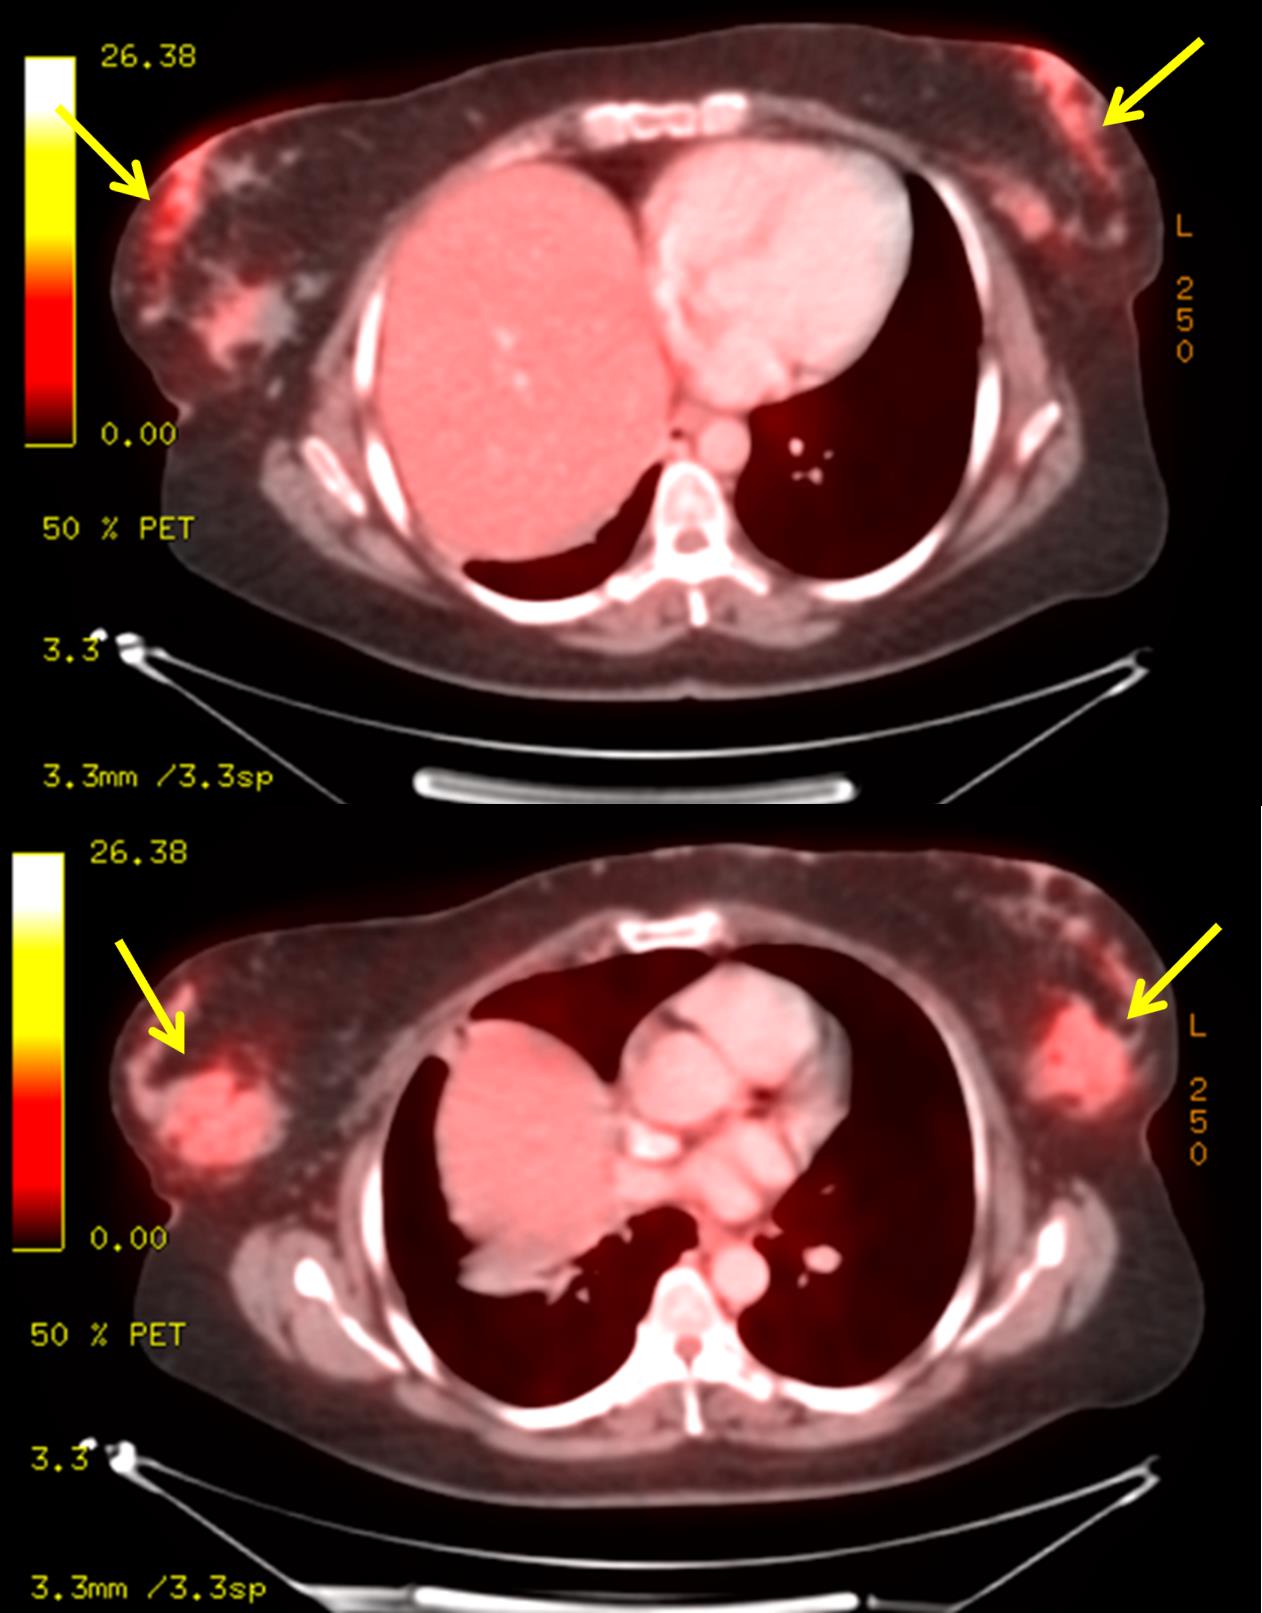

The most common cause of skin metastases in adult women is primary breast carcinoma, which comprises about 70% of cases [1]. Skin metastases have non-specific clinical appearances, making it challenging to differentiate them from other benign conditions [1]. We present a case of a 52-year-old female with type II diabetes and a three-month history of refractory skin lesions who did not respond to anti-inflammatory treatment. The patient subsequently complained of a right breast lump, evaluation of which led to the diagnosis of bilateral synchronous invasive lobular carcinoma.